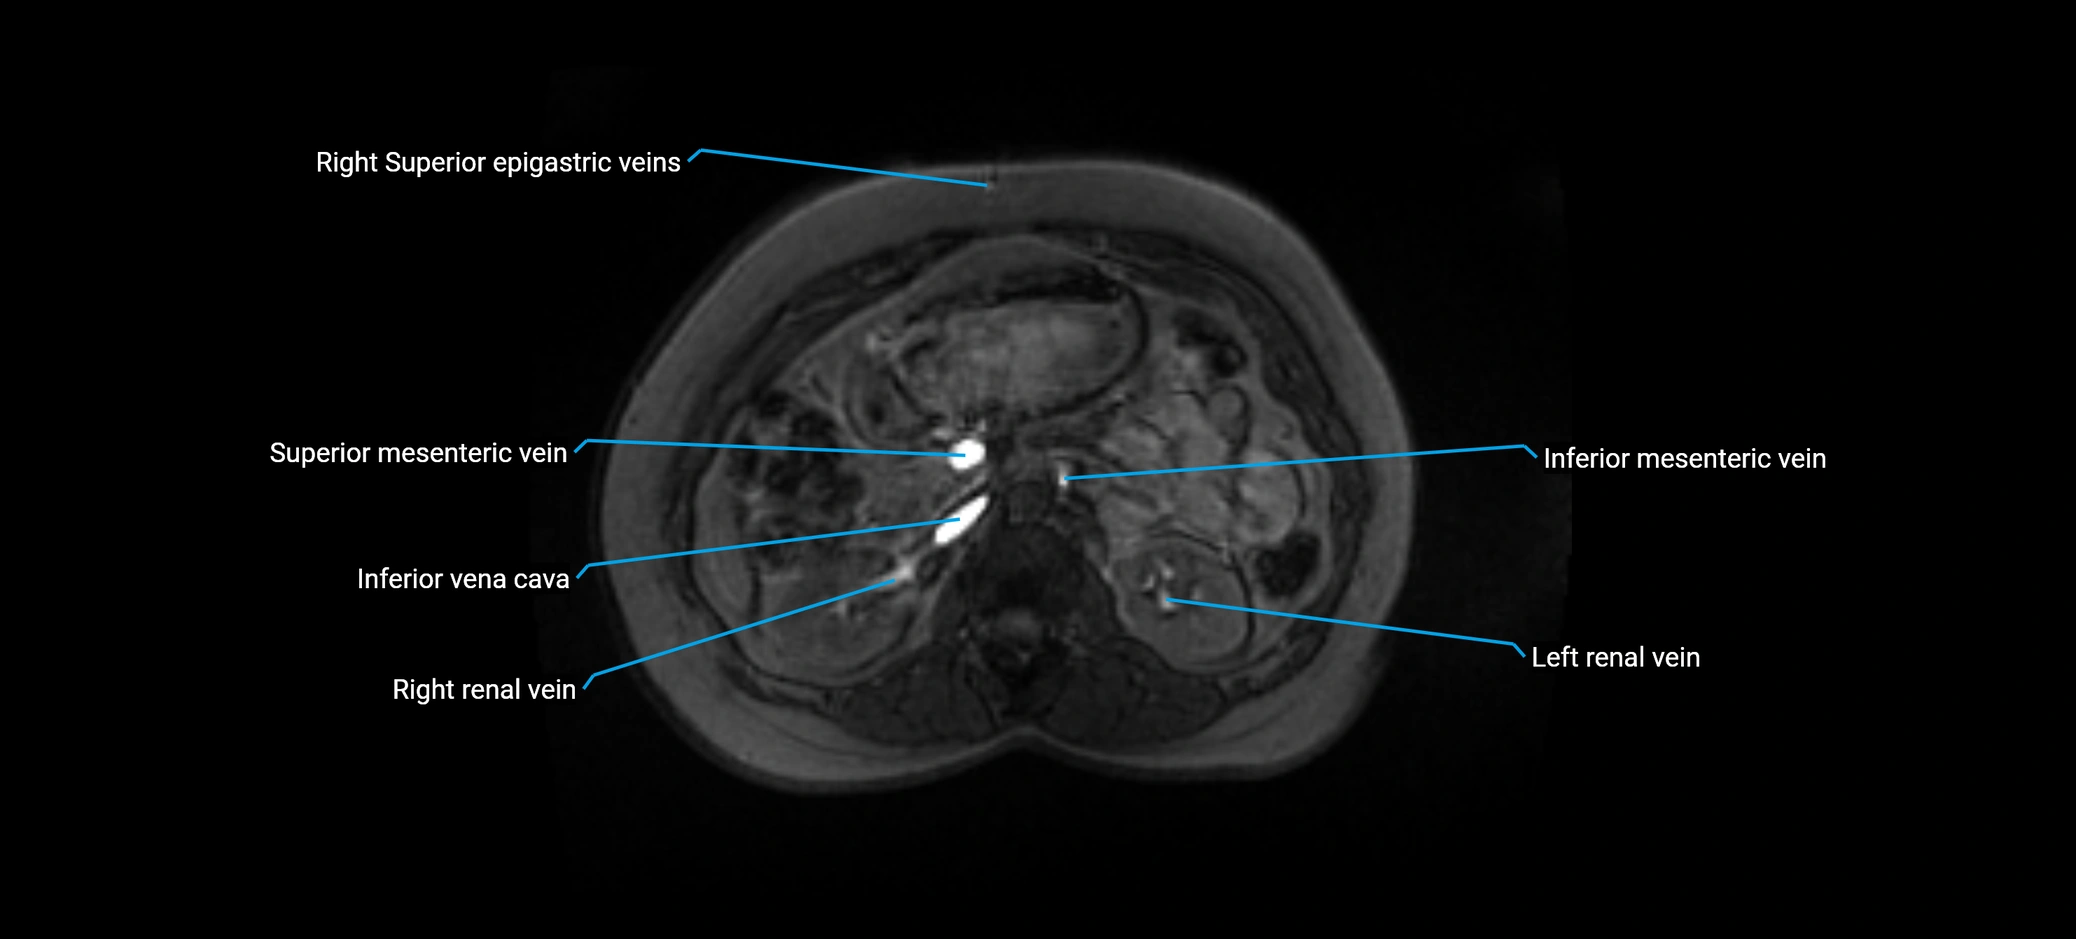

MRI image

image